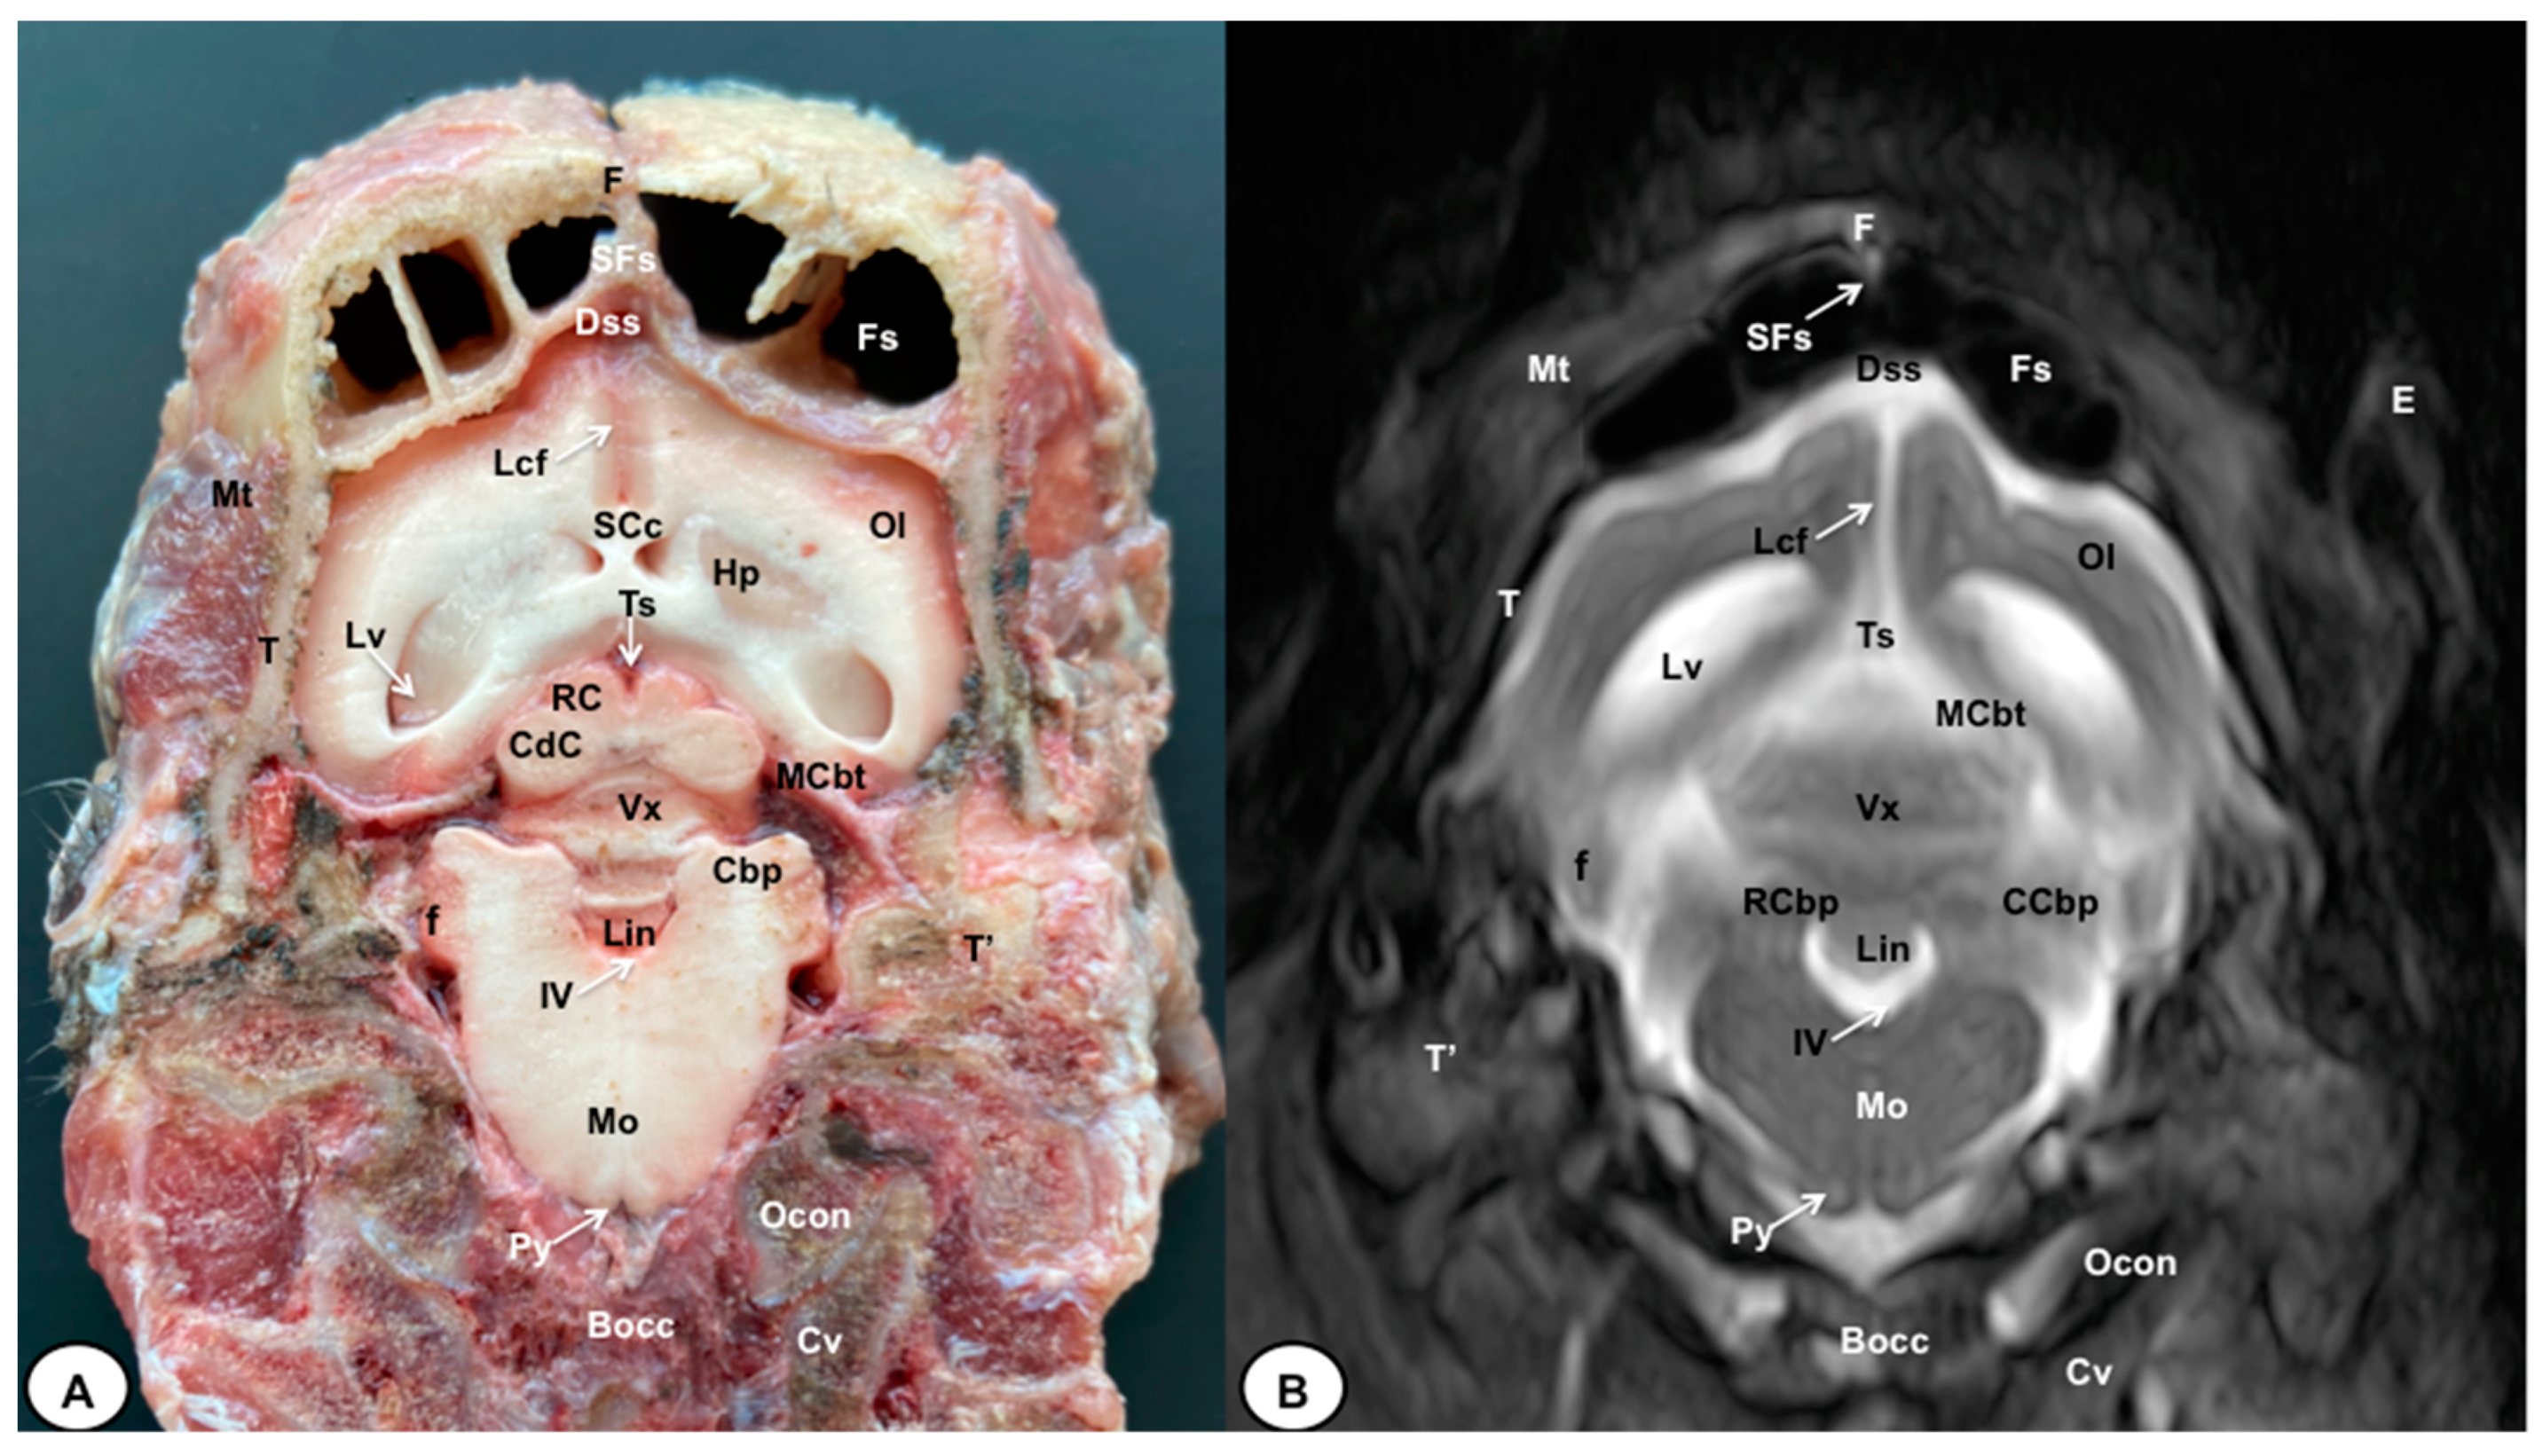

Figure 7.

Transverse cross-section (A) and T2W MR (B) images of the crested porcupine head at the level of the cerebellum, corresponding to line VI in Figure 1. F: frontal bone; Fs: frontal sinuses; SFs: septum of frontal sinuses; T: temporal bone squama; Mt: Musculus temporalis; T′: tympanic and petrous parts of temporal bone; Dss: dorsal sagittal sinus; Lcf: longitudinal cerebral fissure; Lv: lateral ventricle; SCc: splenium of corpus callosum; Hp: hippocampus; Ts: transverse sinus; MCbt: membranous cerebellar tentorium; RC: rostral colliculus; CdC: caudal colliculus; Cbp: cerebellar peduncle; Vx: vermis of cerebellum; RCbp: rostral cerebellar peduncle; CCbp: caudal cerebellar peduncle; Lin: lingula; IV: fourth ventricle; Mo: medulla oblongata; Py: pyramids of the medulla oblongata; Cv: first cervical vertebra; Ocon: occipital condyle; Bocc: basioccipital bone; E: external ear.

The anatomical sections obtained in this study allowed us to visualize the different structures belonging to the central nervous system and its associated structures, which were labeled according to the International Committee on Veterinary Gross Anatomical Nomenclature. Therefore, we identified the main components of the brain (the prosencephalon, mesencephalon, and rhombencephalon). Thus, the two telencephalic hemispheres surrounded by the cerebral cortex and separated by the longitudinal cerebral fissure were identified (Figure 5A, Figure 6A and Figure 7A). Both hemispheres were connected by fibers of white matter known as the corpus callosum (Figure 4A, Figure 5A, Figure 6A and Figure 7A). Each cerebral hemisphere contained a lateral ventricle (Figure 4A, Figure 5A, Figure 6A and Figure 7A). Ventrally, we distinguished a component of the basal ganglia, the nucleus caudatus (Figure 4A and Figure 5A). Thus, we identified different parts of it, such as the head and the tail. Other structures which we observed were the septal nuclei, which were circumscribed by two parallel vertical lines through the most inferior and medial aspect of each lateral ventricle (Figure 4A). More caudally, the diencephalon enclosing the third ventricle was identified, as well as more ventrally specific components of the hypothalamus, such as the optic chiasm (Figure 4A and Figure 5A). Additionally, these sections were quite helpful in showing the caudal parts of the thalamus. Hence, the lateral eminence on the caudodorsal surface of the thalamus, known as the lateral geniculate body, was distinguished, whereas caudoventrally, we identified the medial geniculate body of the thalamus (Figure 5A). Moreover, the dorsal part of the mesencephalon with the caudal and rostral colliculus and its ventral part with the cerebral peduncles were also shown (Figure 6A and Figure 7A). These anatomical sections were helpful in identifying the vermis and the cerebellar peduncles, which connected the cerebellum to the adjacent brain stem and the cerebrum (Figure 7A). The ventral part of the cerebellum with the lingula, covering part of the fourth ventricle, could also be identified (Figure 7A). These sections were also helpful in distinguishing the medulla oblongata and the decussation of the pyramids. In addition, different bony structures comprising the neurocranium were observed, such as the frontal, the temporal (with its scamous, petrous, and tympanic parts), the sphenoid, and the occipital bones (Figure 2A, Figure 3A, Figure 4A, Figure 5A, Figure 6A and Figure 7A). Furthermore, these sections showed different air-filled spaces, such as the frontal and the sphenoidal sinuses (Figure 2A, Figure 3A, Figure 4A, Figure 5A, Figure 6A and Figure 7A), and structures associated with the nasal cavity, including the ethmoturbinates and the vomer, could be distinguished (Figure 2A and Figure 3A). Main sensory organs such as the eyeball and its associated structures were also depicted. Consequently, we identified the retina, the vitreous chamber, and the optic nerve, which were surrounded by extraocular muscles. Among these, we distinguished the dorsal and ventral rectus muscles (Figure 2A). Moreover, the main components of the auditory system, such as the external auditory canal, the tympanic cavity, and the inner ear, were visualized (Figure 5A and Figure 6A). Also, we identified the relevant muscles related to masticatory function, such as the temporalis, the medial and lateral pterygoid muscles, the masseter, the digastric muscle, and other important muscles, including the buccinator muscle and the longissimus capitis of the head (Figure 2A, Figure 3A, Figure 4A, Figure 5A, Figure 6A and Figure 7A).

No significant anatomic differences were identified subjectively in the three porcupines which were imaged. Most anatomic structures distinguished on T2-weighted images of the cadaver specimens matched adequately with structures identified in the corresponding anatomical cross-sections. Hence, the central nervous system structures of the porcupine head, the eyeball’s structures (vitreous humour and lens), and the masticatory muscles showed an accurate visualization using T2W MR images. Nonetheless, the bones that comprised the neurocranium, such as the frontal, the parietal, the temporal, the occipital, and the sphenoid bones, were identified with a hypointense signal (Figure 2B, Figure 3B, Figure 4B, Figure 5B, Figure 6B, Figure 7B, Figure 8 and Figure 9).

In the transverse planes of the encephalon, identifiable structures of the brain were more hyperintense than the white matter, which was more hypointense in T2W sequences (Figure 3B, Figure 4B, Figure 5B, Figure 6B and Figure 7B). Moreover, the two sagittal and dorsal (Figure 8 and Figure 9) images and the different transverse T2W images were essential to depicting the components that comprise the ventricular system, which displayed a hyperintense signal. Hence, the lateral ventricles and the dorsal and ventral parts of the third ventricle were displayed (Figure 4B, Figure 5B, Figure 6B, Figure 7B, Figure 8 and Figure 9), and among these, we observed interthalamic adhesion, limited laterally by the right and left sides of the thalamus (Figure 8A). In addition, transverse, sagittal, and parasagittal T2W images displayed with adequate detail the dorsal and ventral parts of the hippocampus (Figure 5B, Figure 6B, Figure 7B, Figure 8B and Figure 9). In addition, the tectum of mesencephalon (tectum mesencephali) with the caudal colliculus and the fourth ventricle was visualized in excellent detail (Figure 8A,B and Figure 9B). Other essential components of the CNS, such as the vermis of the cerebellum with its dorsal and ventral lobes, were distinguished in the sagittal T2W images (Figure 8A). Hence, the moderate contrast between grey and white matter was helpful in distinguishing the different lobes. Thus, the dorsal lobes of the cerebellum (the rostral and ventral culmen, the declive, the folium, the tuber, and the pyramid), as well as its ventral lobes (the lingula, the nodulus, and the uvula), were identified. In addition to these findings, we also observed the rostral and caudal cerebellar peduncles (Figure 7B and Figure 9A). This technique also facilitated an adequate resolution to be achieved with which to identify the muscles involved in the masticatory function, which have already been mentioned in the anatomical sections.